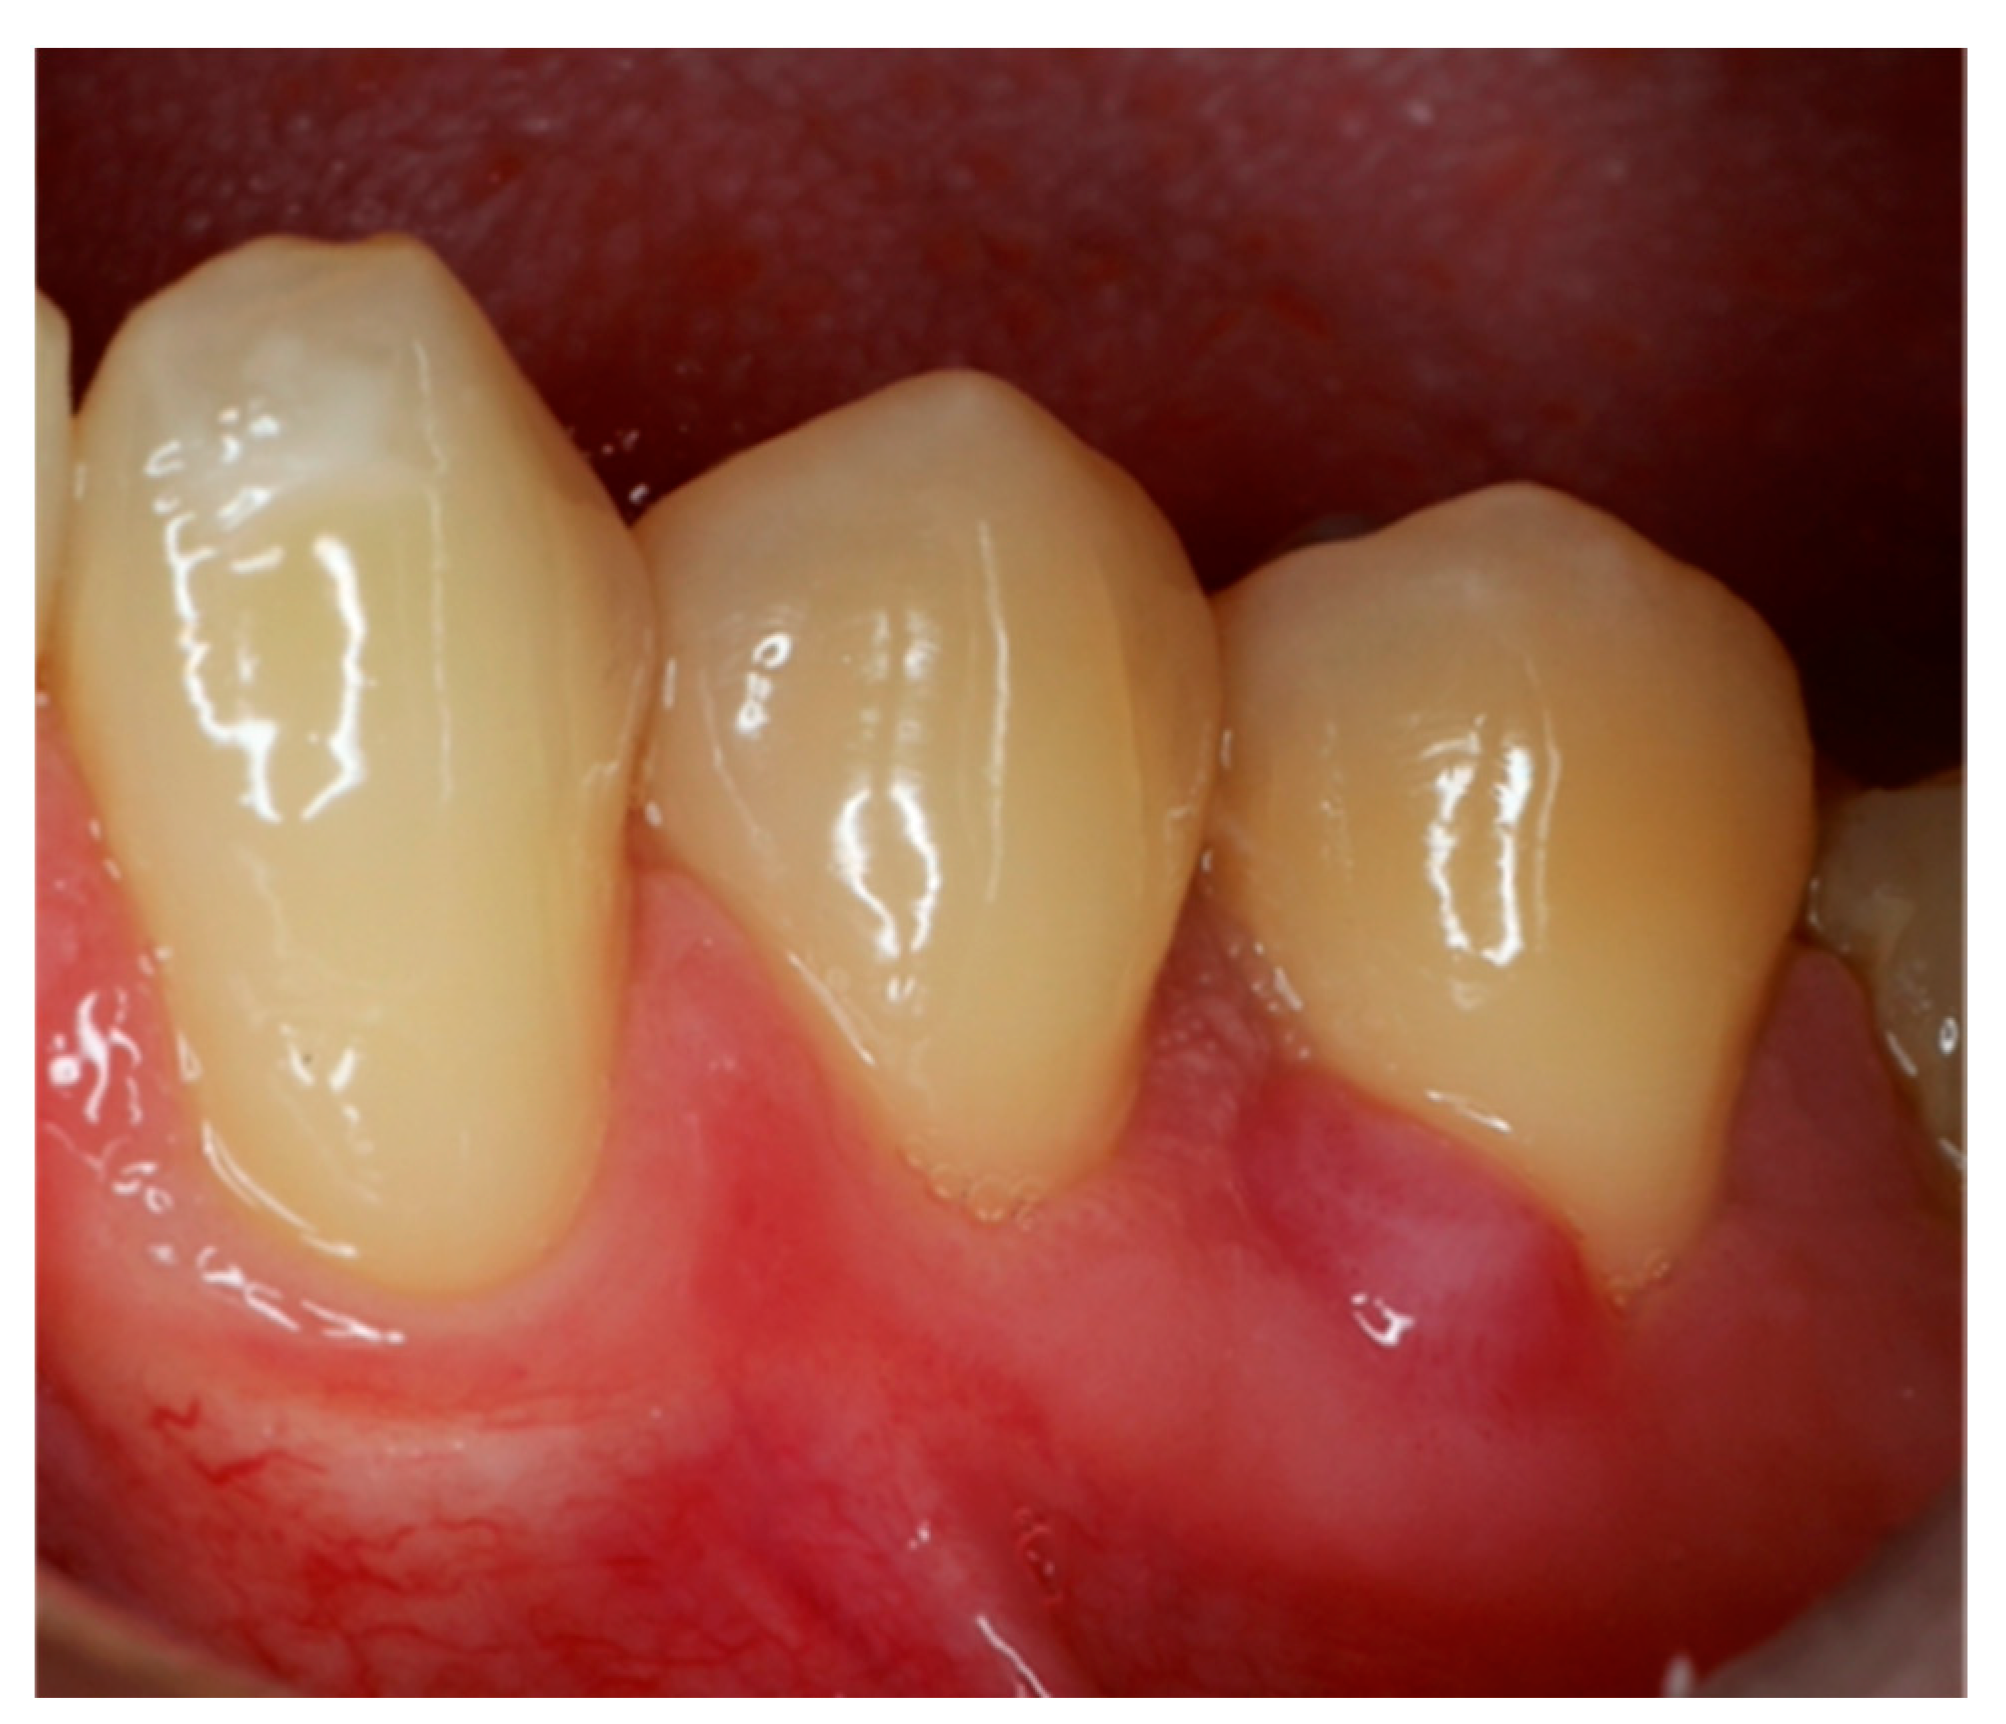

2. Case Report